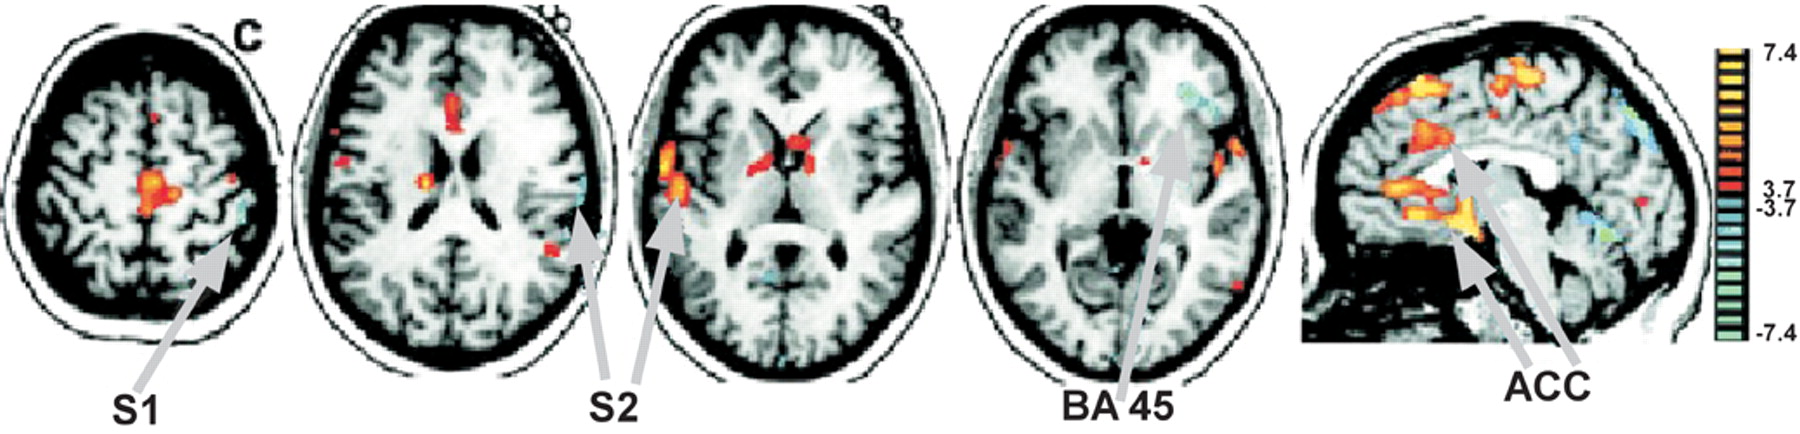

“Despite a long-held scientific belief that much of the wiring of the brain is fixed by the time of adolescence, a new study shows that changes in sensory experience can cause massive rewiring of the brain, even as one ages. In addition, the study found that this rewiring involves fibers that supply the primary input to the cerebral cortex, the part of the brain that is responsible for sensory perception, motor control and cognition. These findings promise to open new avenues of research on brain remodeling and aging.”

“This study overturns decades-old beliefs that most of the brain is hard-wired before a critical period that ends when one is a young adult,” said MPFI neuroscientist Marcel Oberlaender, PhD, first author on the paper. “By changing the nature of sensory experience, we were able to demonstrate that the brain can rewire, even at an advanced age. This may suggest that if one stops learning and experiencing new things as one ages, a substantial amount of connections within the brain may be lost.”